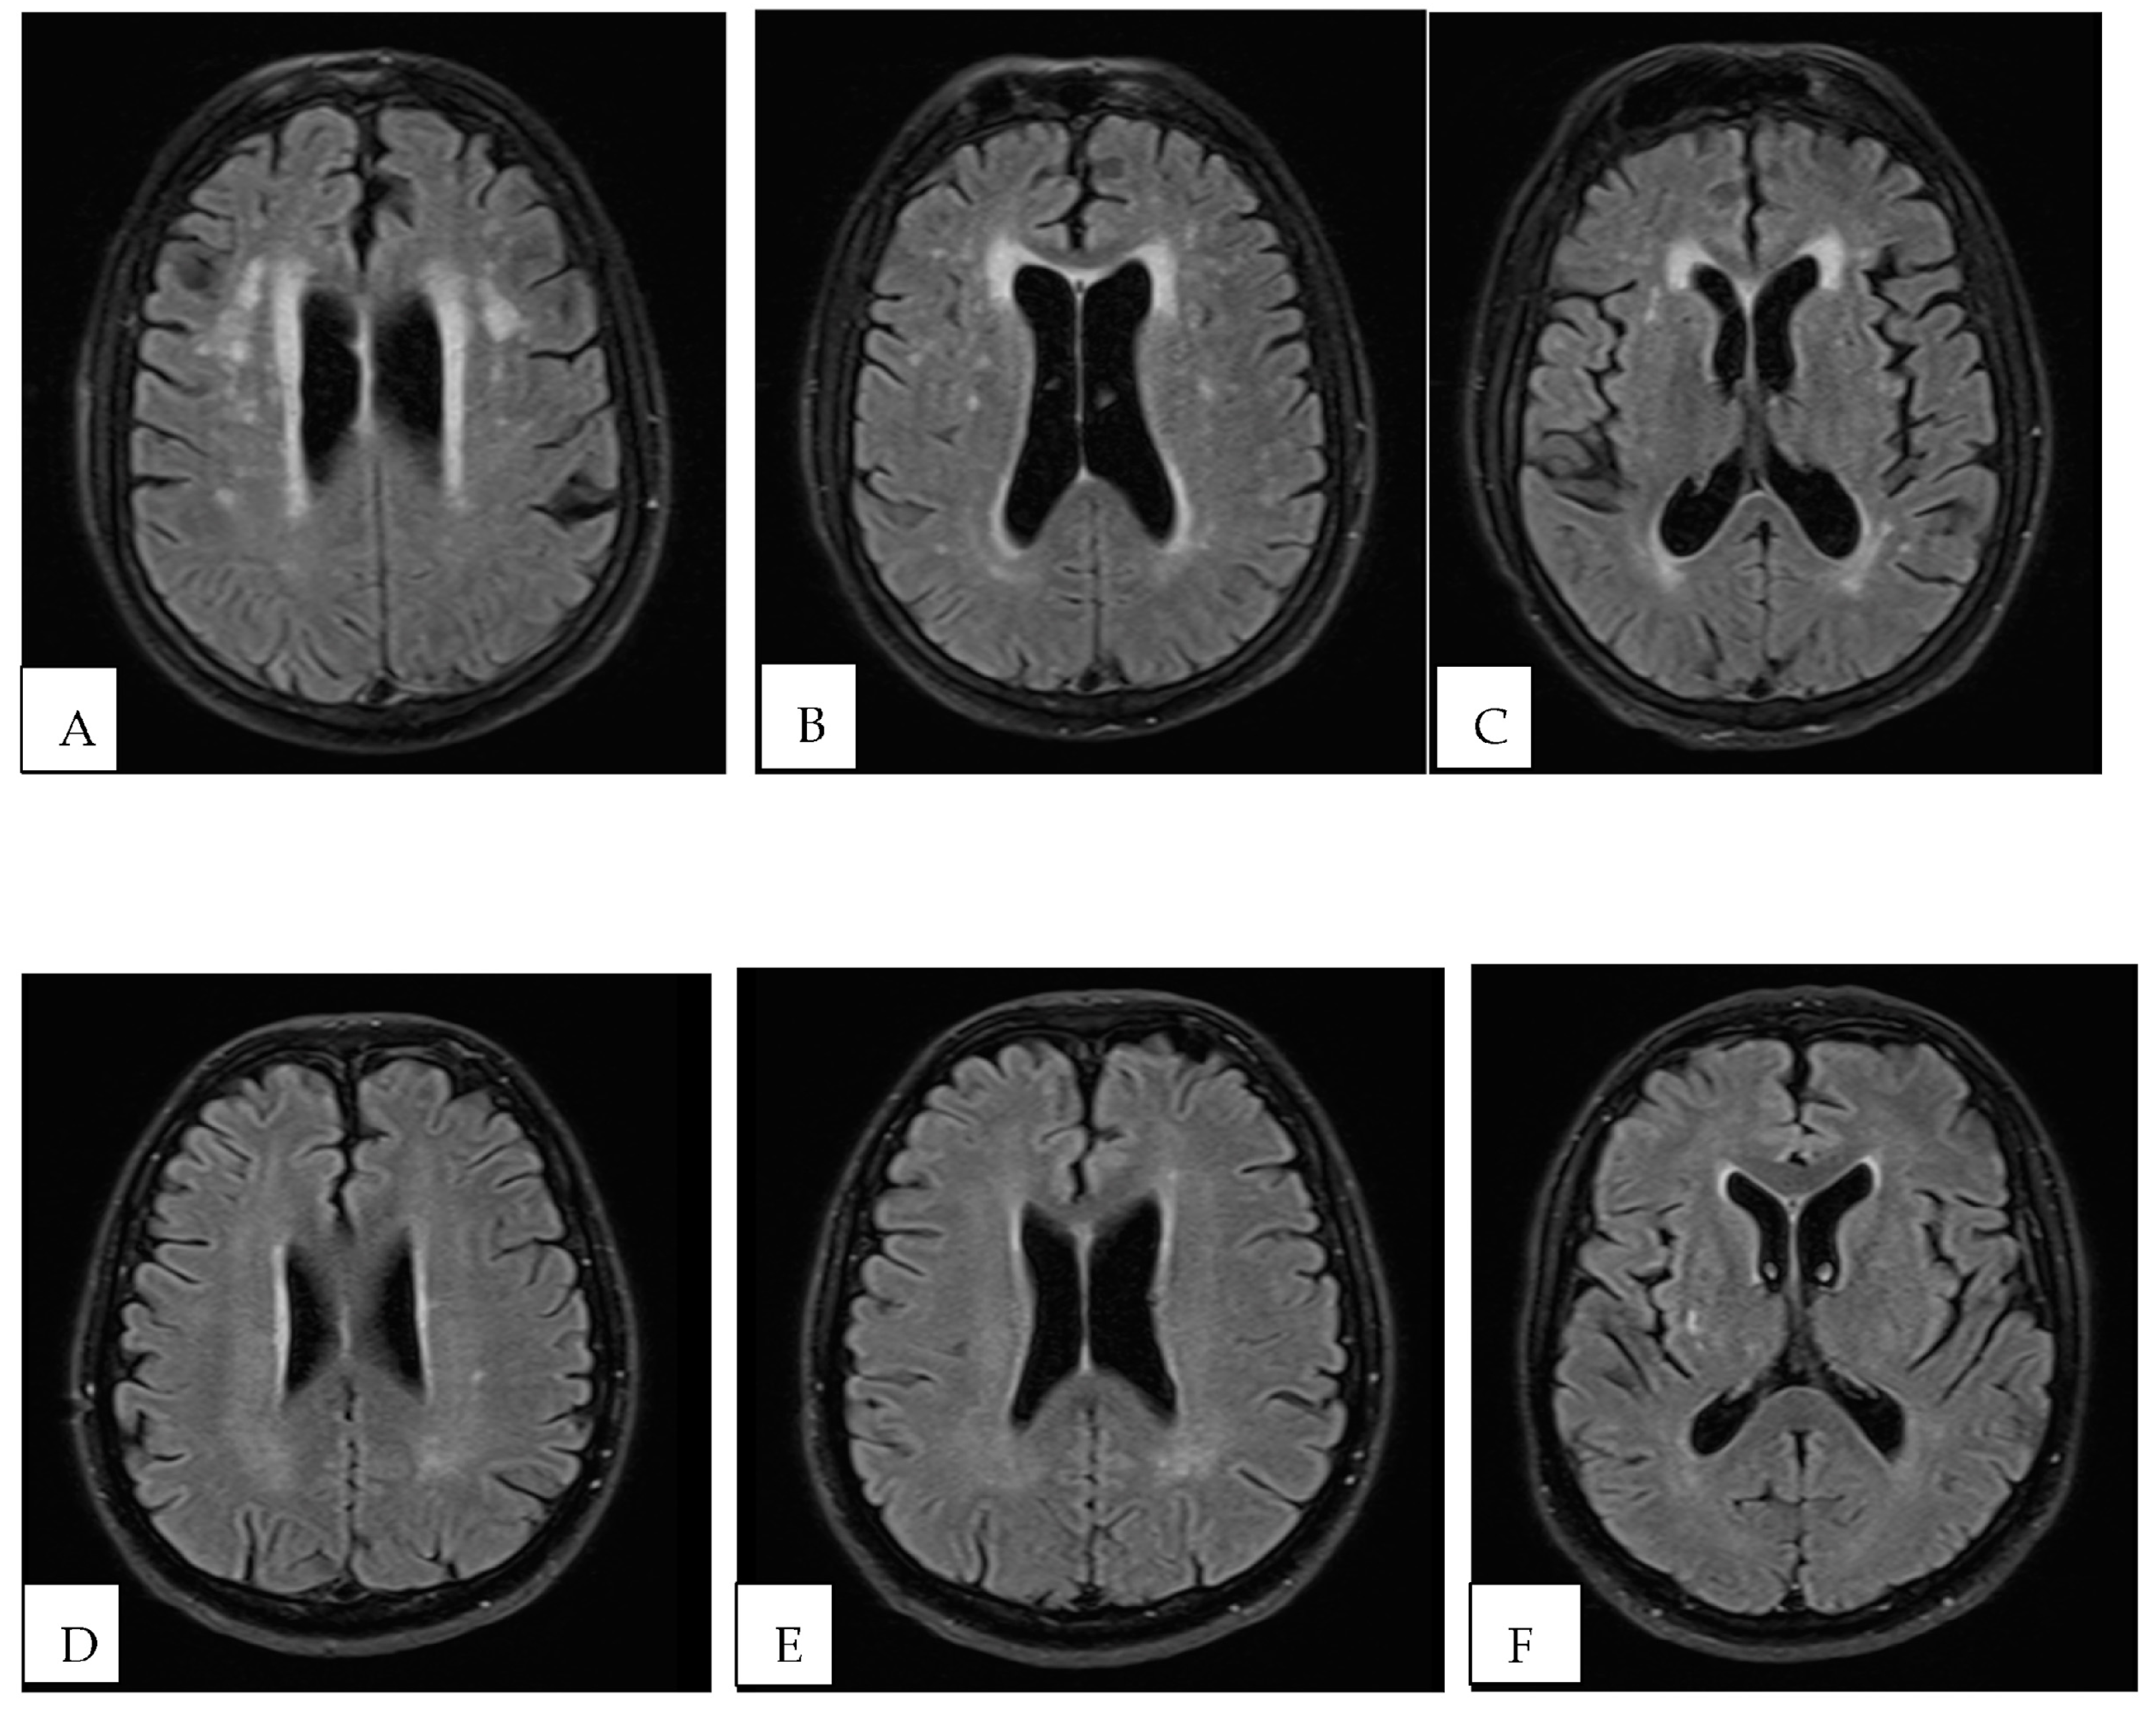

- Kim, T.W.; Kim, Y.-H.; Kim, K.H.; Chang, W.H. White Matter Hyperintensities and Cognitive Dysfunction in Patients with Infratentorial Stroke. Ann. Rehabil. Med. 2014, 38, 620–627. [Google Scholar] [CrossRef]

| Fazekas scale n (%) | 17 (100) | 8 (47.1) | 9 (52.9) | 0.127 |

| 0 n (%) | 6 (35.3) | 2 (25.0) | 4 (44.5) | |

| 1 n (%) | 8 (47) | 3 (37.5) | 5 (55.6) | |

| 2 n (%) | 3 (17.7) | 3 (37.5) | 0 (0.00) | |

| 3 n (%) | 0 (0.0) | 0 (0.00) | 0 (0.00) |

| Fazekas scale n (%) | 17 (100) | 8 (47.1) | 9 (52.9) | 0.012 |

| 0 n (%) | 6 (35.3) | 1 (20) | 5 (41.7) | |

| 1 n (%) | 8 (47) | 1 (20) | 7 (58.3) | |

| 2 n (%) | 3 (17.7) | 3 (60) | 0 (0.0) | |

| 3 n (%) | 0 (0.0) | 0 (0.0) | 0 (0.0) | |